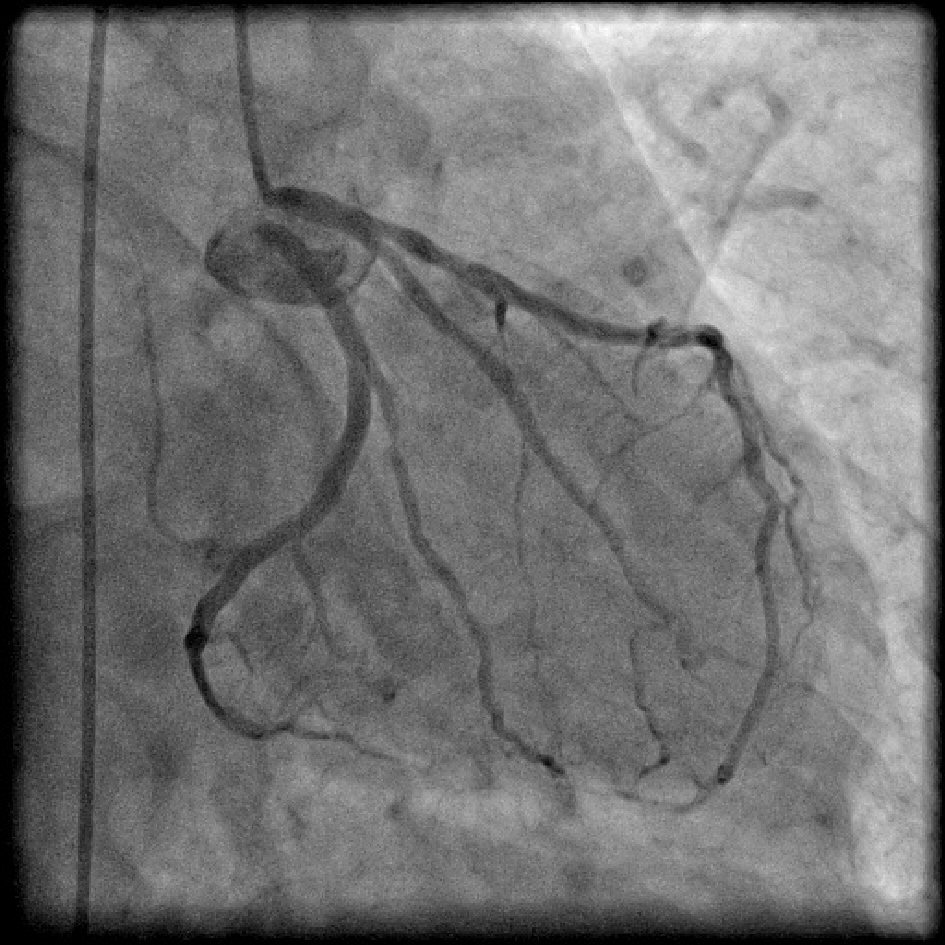

Split RCA (Fig. 5) was the most common coronary anomaly detected in the study, being seen in 27 patients, with an angiographic incidence of 0.84% and anomaly incidence of 27.27%. Dual LAD (Fig. 6) was the second most common anomaly being seen in 22 cases with an angiographic incidence of 0.68% and anomaly incidence of 22.22%. Superdominant LAD supplying the posterior descending artery (PDA) (Fig. 7) was seen in one patient, with an angiographic incidence of 0.03% and anomaly incidence of 1.01%.

![]() Click for large image | Figure 6. Coronary angiogram in right anterior oblique (RAO) cranial projection showing type I dual left anterior descending artery (LAD). |

![]() Click for large image | Figure 7. Coronary angiogram in right anterior oblique (RAO) cranial projection showing superdominant left anterior descending artery (LAD) continuing as posterior descending artery (PDA). Temporary pacing lead is seen in right ventricle (RV) apex as patient had third degree atrioventricular (AV) block. |